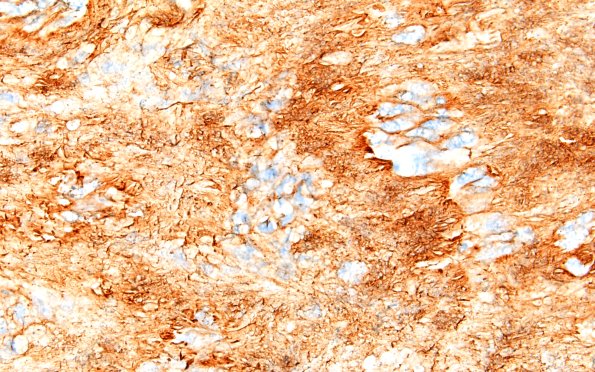

Washington University Experience | NEOPLASMS - CRANIAL AND PARASPINAL NERVEs | Schwannoma | 32C4 Schwannoma (Case 32) Coll IV 60X

Higher magnification of the tumor showing strong collagen IV immunoreactivity in a Verocay body. (Collagen IV IHC)